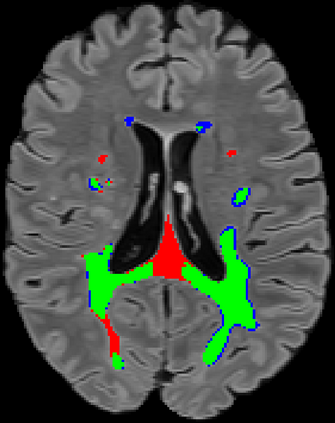

Recently, segmentation methods based on Convolutional Neural Networks (CNNs) showed promising performance in automatic Multiple Sclerosis (MS) lesions segmentation. These techniques have even outperformed human experts in controlled evaluation conditions such as Longitudinal MS Lesion Segmentation Challenge (ISBI Challenge). However state-of-the-art approaches trained to perform well on highly-controlled datasets fail to generalize on clinical data from unseen datasets. Instead of proposing another improvement of the segmentation accuracy, we propose a novel method robust to domain shift and performing well on unseen datasets, called DeepLesionBrain (DLB). This generalization property results from three main contributions. First, DLB is based on a large group of compact 3D CNNs. This spatially distributed strategy ensures a robust prediction despite the risk of generalization failure of some individual networks. Second, DLB includes a new image quality data augmentation to reduce dependency to training data specificity (e.g., acquisition protocol). Finally, to learn a more generalizable representation of MS lesions, we propose a hierarchical specialization learning (HSL). HSL is performed by pre-training a generic network over the whole brain, before using its weights as initialization to locally specialized networks. By this end, DLB learns both generic features extracted at global image level and specific features extracted at local image level. DLB generalization was validated in cross-dataset experiments on MSSEG'16, ISBI challenge, and in-house datasets. During experiments, DLB showed higher segmentation accuracy, better segmentation consistency and greater generalization performance compared to state-of-the-art methods. Therefore, DLB offers a robust framework well-suited for clinical practice.